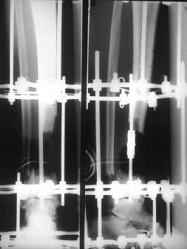

Огнестрельный дефект костей и передней группы мышц, поступил с юнилатеральным аппаратом, стабильность плохая, из раны обильное гнойное

отделяемое. #1;#2. Стержневой апп. снят, наложен апп. Илизарова, дренажно-ирригационная система промывки раны. #3; #4. После стихания инфекции,

аппаратом постепенно создана рекурвация для сближения контактов мышц (сухожилий) передней группы голени. #5;#6. Наложен шов на сухожлилия М.

Tibialis anterior и M extensor digitorum L. Одновременно компактотомия костей голени в В/3 для замешение дефекта костей. #7;#8. Постепенно

исправлена ось и возмещен дефект. В результате восстановление тыльной флекcии стопы и функции конечности. #9;#10;#11